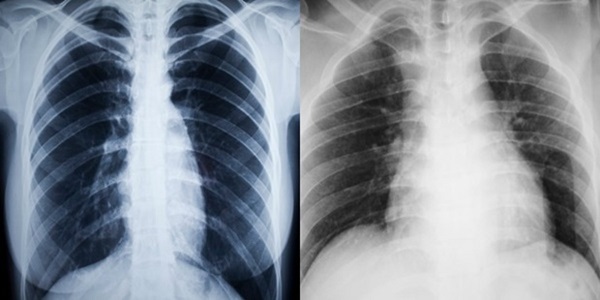

Εδώ βλέπετε την ακτινογραφία ενός ατόμου που δεν καπνίζει και έχει υγιείς πνεύμονες (αριστερά) και την αντίστοιχη ακτινογραφία ενός ατόμου που είναι χρόνιος καπνιστής και έχει κατεστραμμένους πνεύμονες (δεξιά).

Το κάπνισμα καταστρέφει τον πνευμονικό ιστό και αυτό είναι άμεσα ορατό στον καθένα. Ο καπνός από το τσιγάρο περιέχει περίπου 4.000 χημικές ουσίες, συμπεριλαμβανομένου του μονοξειδίου του άνθρακα. Αυτό δυσχεραίνει πολύ την λειτουργία των πνευμόνων και εμποδίζει το πολύτιμο οξυγόνο να κυκλοφορεί σωστά μέσα στο σώμα. Οι χημικές ουσίες στον καπνό του τσιγάρου ερεθίζουν και προκαλούν φλεγμονή στους αεραγωγούς και τους πνεύμονες.

Αυτές οι χημικές ουσίες “αφοπλίζουν” το φυσικό αμυντικό σύστημα των πνευμόνων. Μικροσκοπικές τρίχες στους αεραγωγούς, που ονομάζονται “βλεφαρίδες των πνευμόνων”, φιλτράρουν κανονικά τις τοξίνες και άλλα βακτήρια που εισέρχονται σε αυτούς, αλλά το κάπνισμα τις καταστρέφει. Αυτό έχει ως αποτέλεσμα διάφορες τοξίνες και βακτήρια να φτάνουν και να αναπαράγονται μέσα στους πνεύμονες.